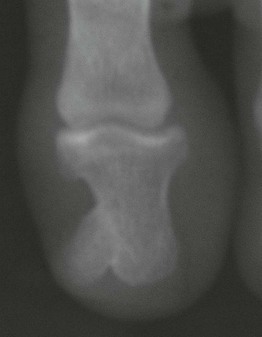

• Bulbous digits with watch-glass nails (> 180° angle between proximal nail fold and nail).

• Most commonly seen in thyroid acropachy and in association with cardiovascular and bronchopulmonary disorders.